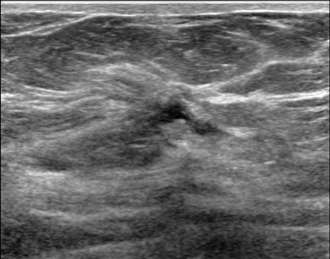

The ultrasound image above demonstrates sonographic architectural distortion. The hyperechoic (bright) bands of tissue interdigitating between the fat in the breast become focally altered and seem to radiate around a small lesion. Biopsy revealed a complex sclerosing lesion (sometimes called a radial scar) which is a benign, but sometimes high risk lesion, which can be recognized as architectural distortion on ultrasound. Other examples of benign causes of architectural distortion include sclerosing adenosis, fat necrosis, post-procedural changes, granular cell tumors, and breast fibromatosis. Architectural distortion may also be associated with breast cancer, as evidenced by the example below: